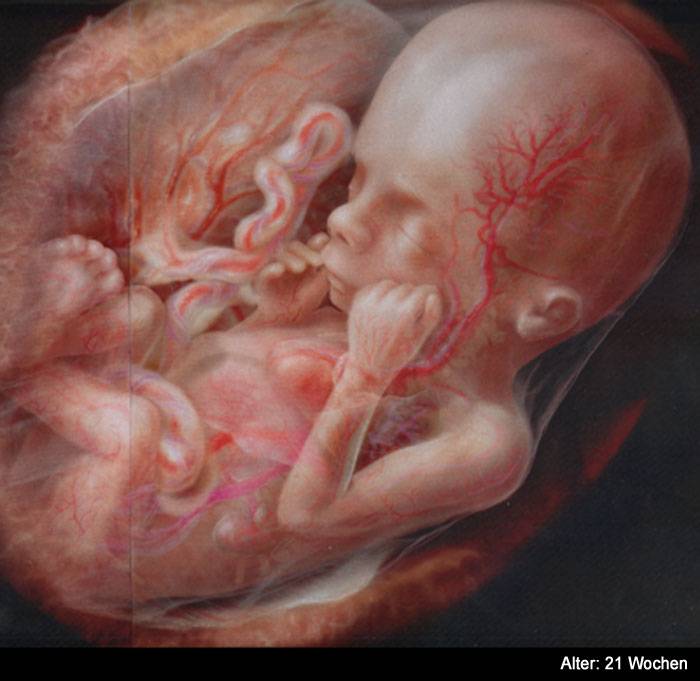

25 недель беременности: Как выглядит будущий малыш

Раздел: Образы вокруг